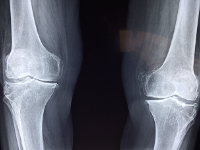

4. 무릎 변형

무릎 관절염은 심해지면 무릎의 모양이 변형될 수 있습니다. 무릎이 안쪽으로 꺾이거나 바깥쪽으로 튀어나오는 현상이 나타날 수 있습니다. 이러한 변형은 연골과 인대가 손상되어 관절의 안정성이 깨지거나, 근육의 힘이 약해져서 발생할 수 있습니다.